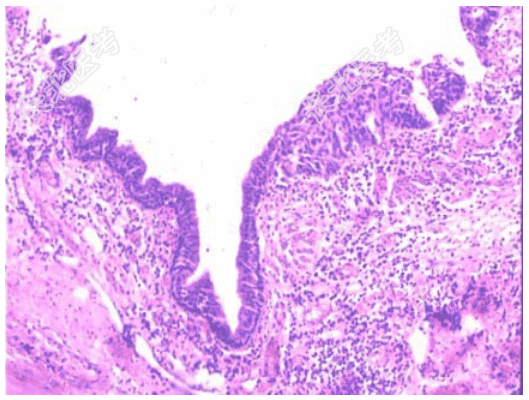

- [材料题] 患者,男,55岁,每年冬春季节均会出现反复发作的咳嗽、咳痰等症状,至少持续3个月以上。胸片示肺纹理增粗,紊乱。

- 简答题1、纤支镜取活检镜下如图所示,该患者正确的诊断是?